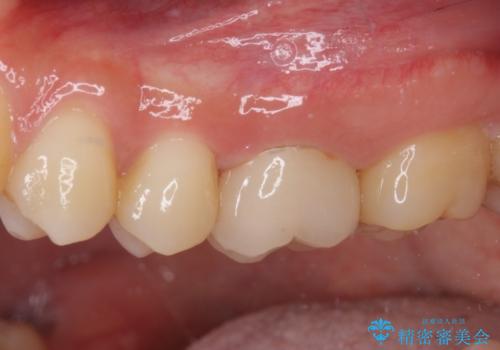

虫歯は深くまで進行しており、歯冠部の神経から出血が認められました。神経を部分的に除去したところ出血が治まったので、生体親和性の非常に高いセメントにて充填し、仮封をしました。

後日状態を確認したところ、残された神経に異常がなかったため、セラミッククラウンにて補綴治療を行いました。